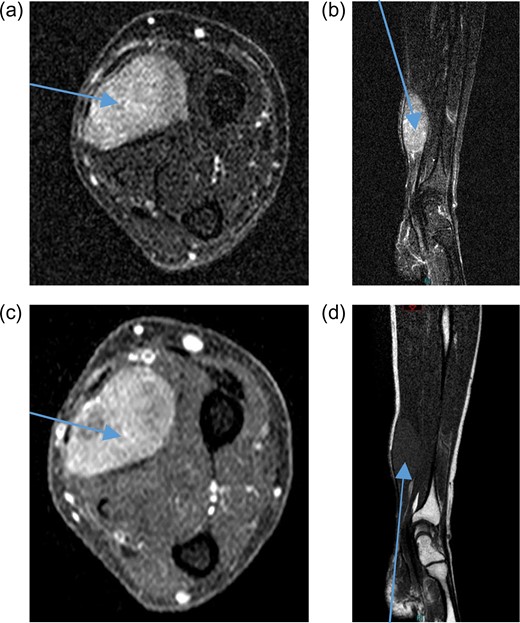

A 71-year-old male was referred to sarcoma clinic on 11/9/2017 with a painless swelling in his right forearm. He had a previous history of primary retro-peritoneal leiomyosarcoma surgery in 2011 with subsequent liver and lung metastases for which he underwent surgical resection in January 2017. His other past medical history included benign prostatic hypertrophy (controlled with medication), otherwise he was fully mobile, fit and well. This right-hand dominant male described a gradual 3-month history of increasing painless swelling to the volar aspect of the right forearm with full function of the arm and no neurological deficit. On clinical examination, there was a soft 5 × 4 cm swelling, 5 cm proximal to wrist crease in the volar compartment of the right forearm. The swelling was fixed, non-tender with no distal neurovascular deficit and or regional lymphadenopathy. Magnetic resonance imaging (MRI) of the right forearm demonstrated a 45 × 33 × 19 mm mass in the volar aspect in close relation to the median nerve (Fig. 1). Ultrasound-guided needle core biopsy was consistent with LMS and the histology was similar to the previous LMS suggesting the possibility of metastatic LMS. Staging studies did not show any other metastatic deposits. Following multidisciplinary team discussion, he underwent planned marginal excision of the metastatic sarcoma with preservation of the median nerve. Histology confirmed LMS composed of spindle cells with eosinophilic cytoplasm with mild pleomorphism confined within the perimysium with no necrosis or vascular invasion (trojani grade 1). The patient recovered well post operatively with no neurological deficit only complicated with a mild episode of cellulitis to the wound site which fully resolved with a short course of oral antibiotics. One year after surgery, the patient has full function and use of his right hand and there is no evidence of LMS recurrence or further metastatic spread both clinically and radiologically on recent CT scan of his chest, abdomen and pelvis and MRI scan of the forearm (Fig. 2).

Pre-treatment contrast MRI of forearm showing large soft-tissue mas lesion involving the flexor aspect of right forearm (a) axial T2, (b) coronal T2, (c) axial T1 and (d) coronal T1.